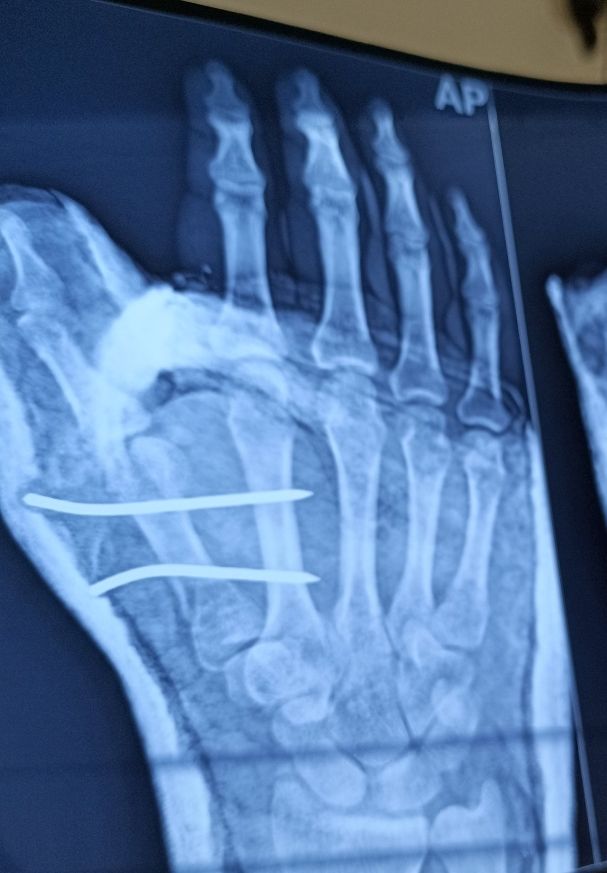

Kwire fixation to metacarpal fractures. Download Scientific Diagram K Wire Procedure They can be placed percutaneously (through the skin) or can be buried beneath the skin. Introduced in 1909 by martin kirschner, the. K wire fixation of hand fractures. K wire (kirschner wire) is passed through the skin then transversely through the bone and out the other side of the limb. Each method has its advantages and disadvantages. These wires can. K Wire Procedure.

Pls Rx for K wire procedure in right hand's thumb metacarpal K Wire Procedure These wires can be drilled through the bone to hold the fragments in place. Each method has its advantages and disadvantages. K wire (kirschner wire) is passed through the skin then transversely through the bone and out the other side of the limb. Introduced in 1909 by martin kirschner, the. K wire fixation of hand fractures. The wire is then. K Wire Procedure.

Pls Rx for K wire procedure in right hand's thumb metacarpal K Wire Procedure K wire fixation of hand fractures. Each method has its advantages and disadvantages. K wire (kirschner wire) is passed through the skin then transversely through the bone and out the other side of the limb. The wire is then attached to some form of traction so that the pull is applied directly to bone. These wires can be drilled through. K Wire Procedure.